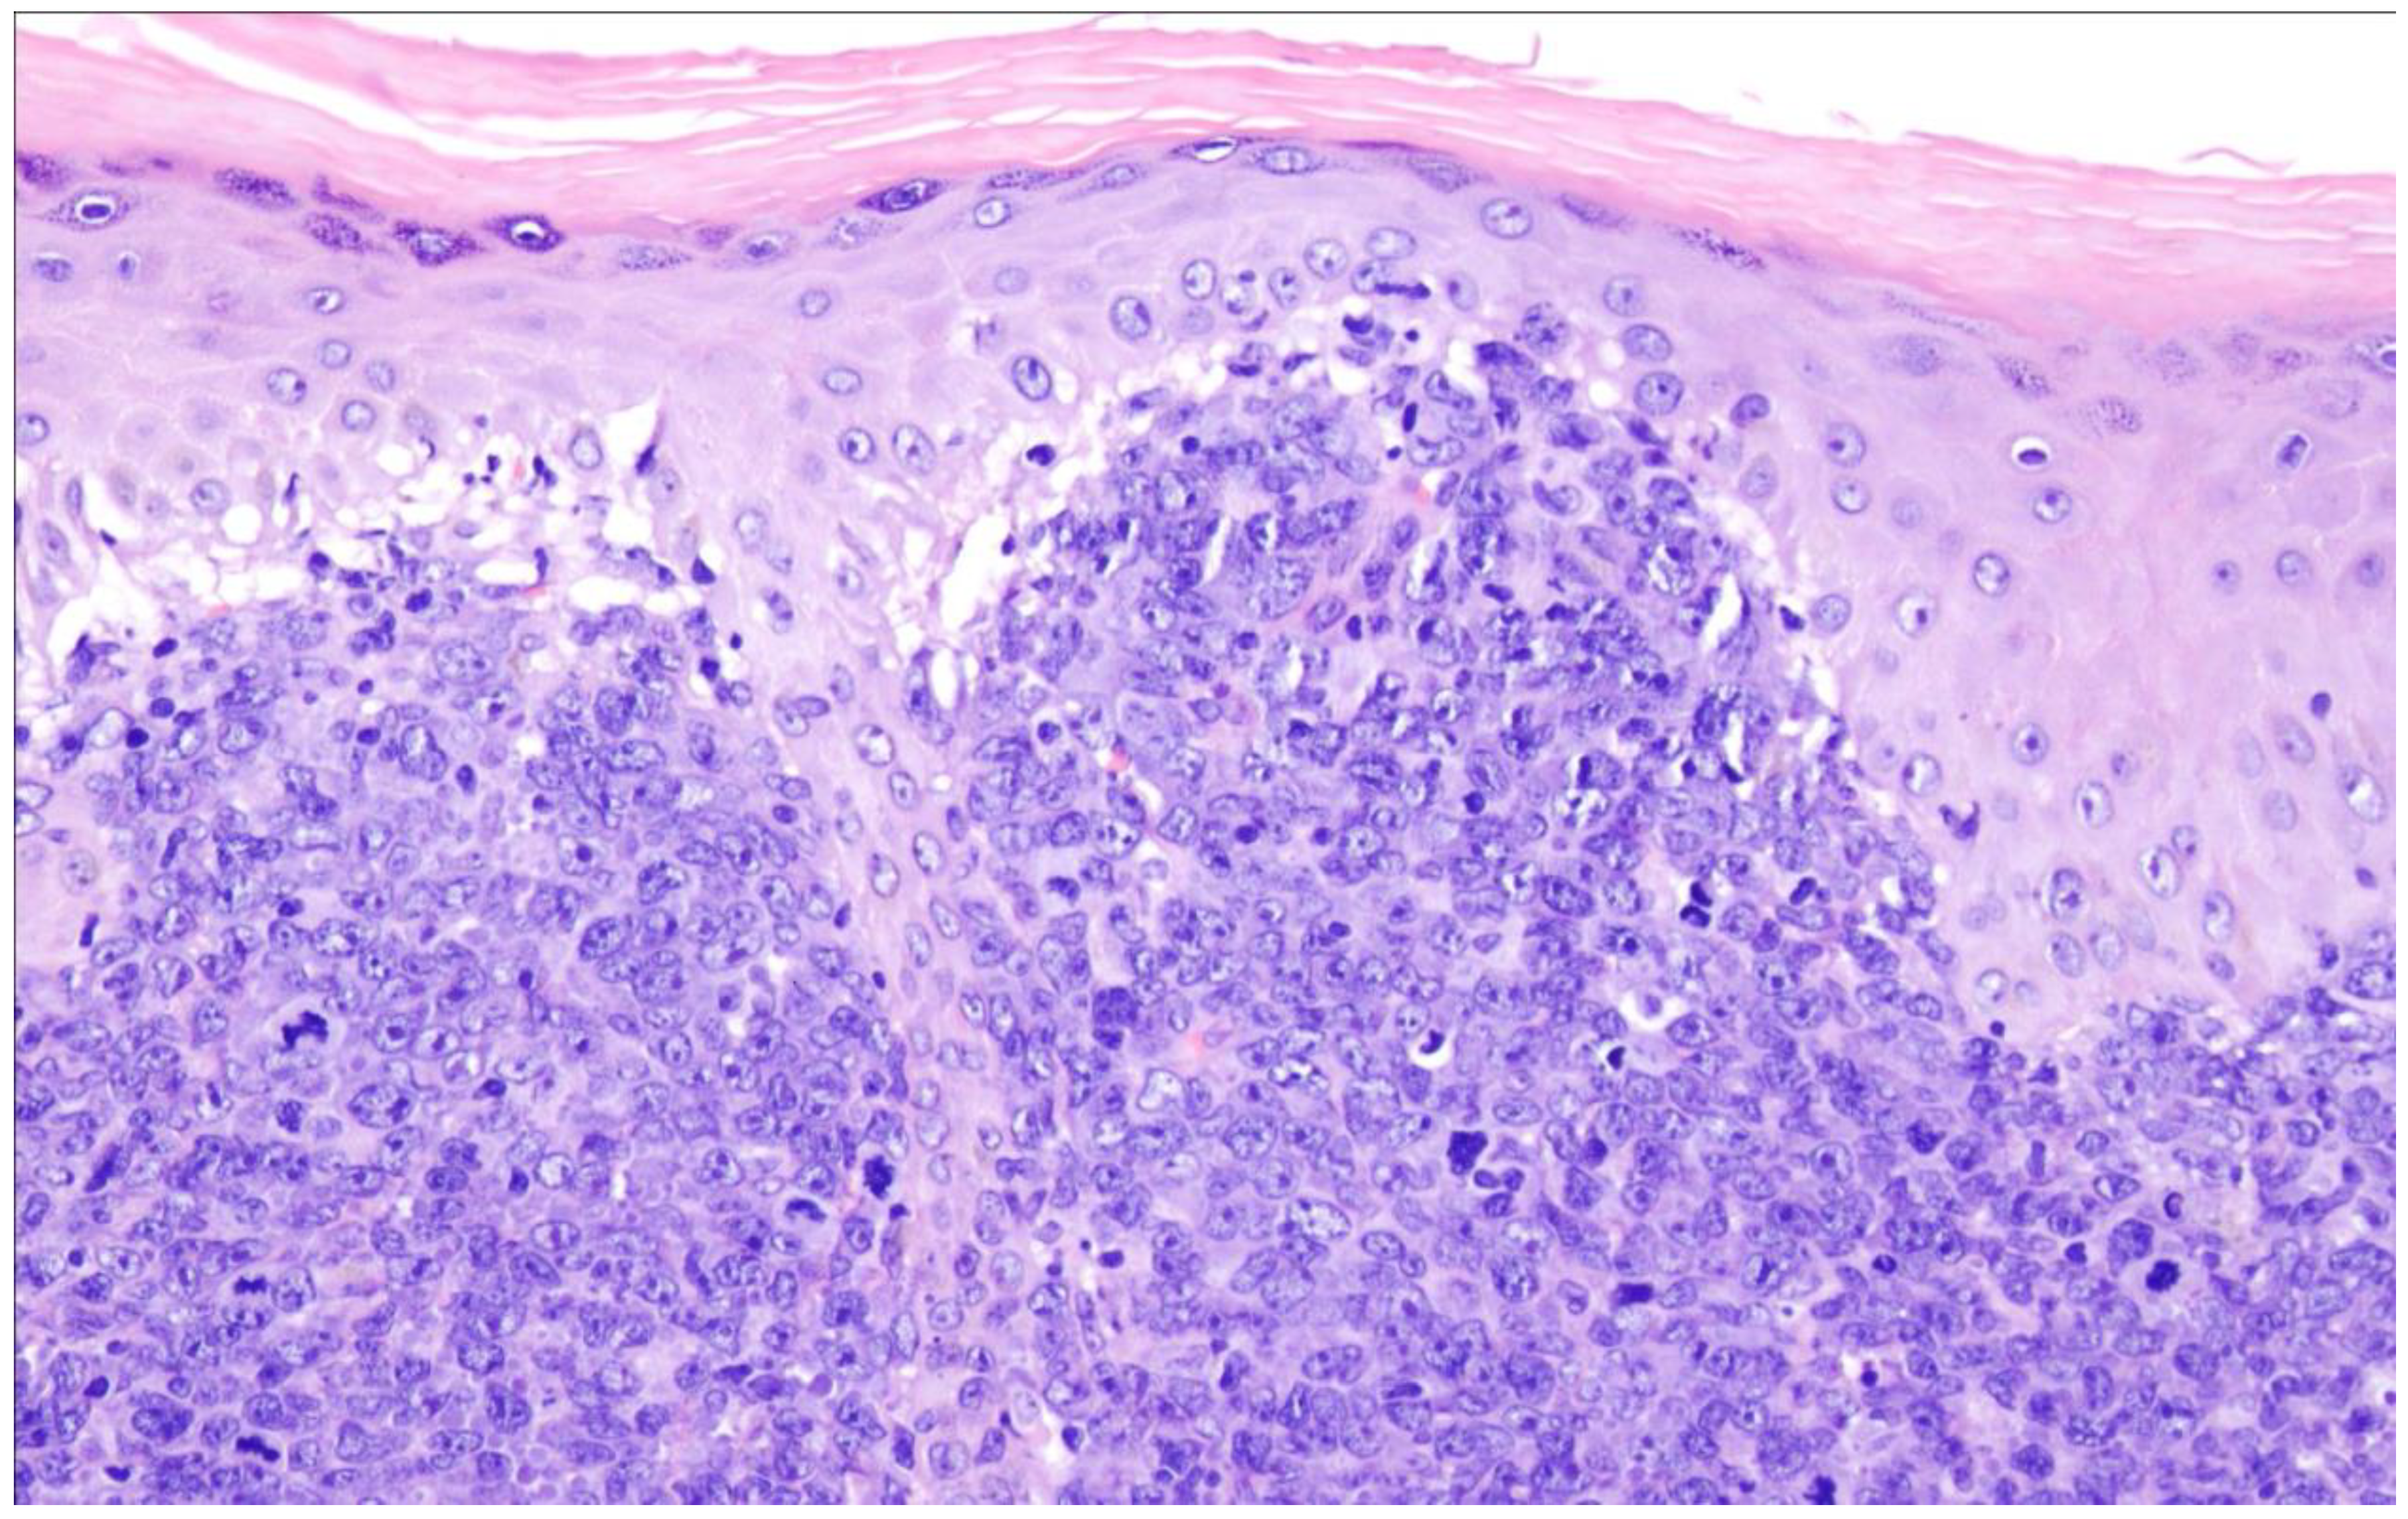

16. Primary Cutaneous Diffuse Large B-Cell Lymphoma, Leg Type

| Primary cutaneous diffuse large B-cell lymphoma, leg type |